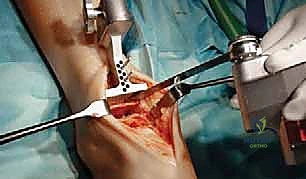

تُجرى العملية عادة تحت التخدير العام أو التخدير النصفي (الشوكي). يقوم د. هطيف بعمل شق جراحي أمامي أو جانبي (حسب التقنية المستخدمة وحالة المريض) للوصول إلى مفصل الكاحل بعناية، مع الحفاظ على الأوتار والأعصاب والأوعية الدموية المحيطة.

3. إزالة الأسطح التالفة (تحضير العظام)

باستخدام أدوات جراحية دقيقة وموجهات خاصة، يتم إزالة الغضاريف التالفة وجزء رقيق جداً من العظام المريضة من نهايتي عظمة الظنبوب وعظمة الكاحل (Talus). يتم تشكيل العظام بدقة لتتطابق تماماً مع شكل أجزاء المفصل الصناعي.